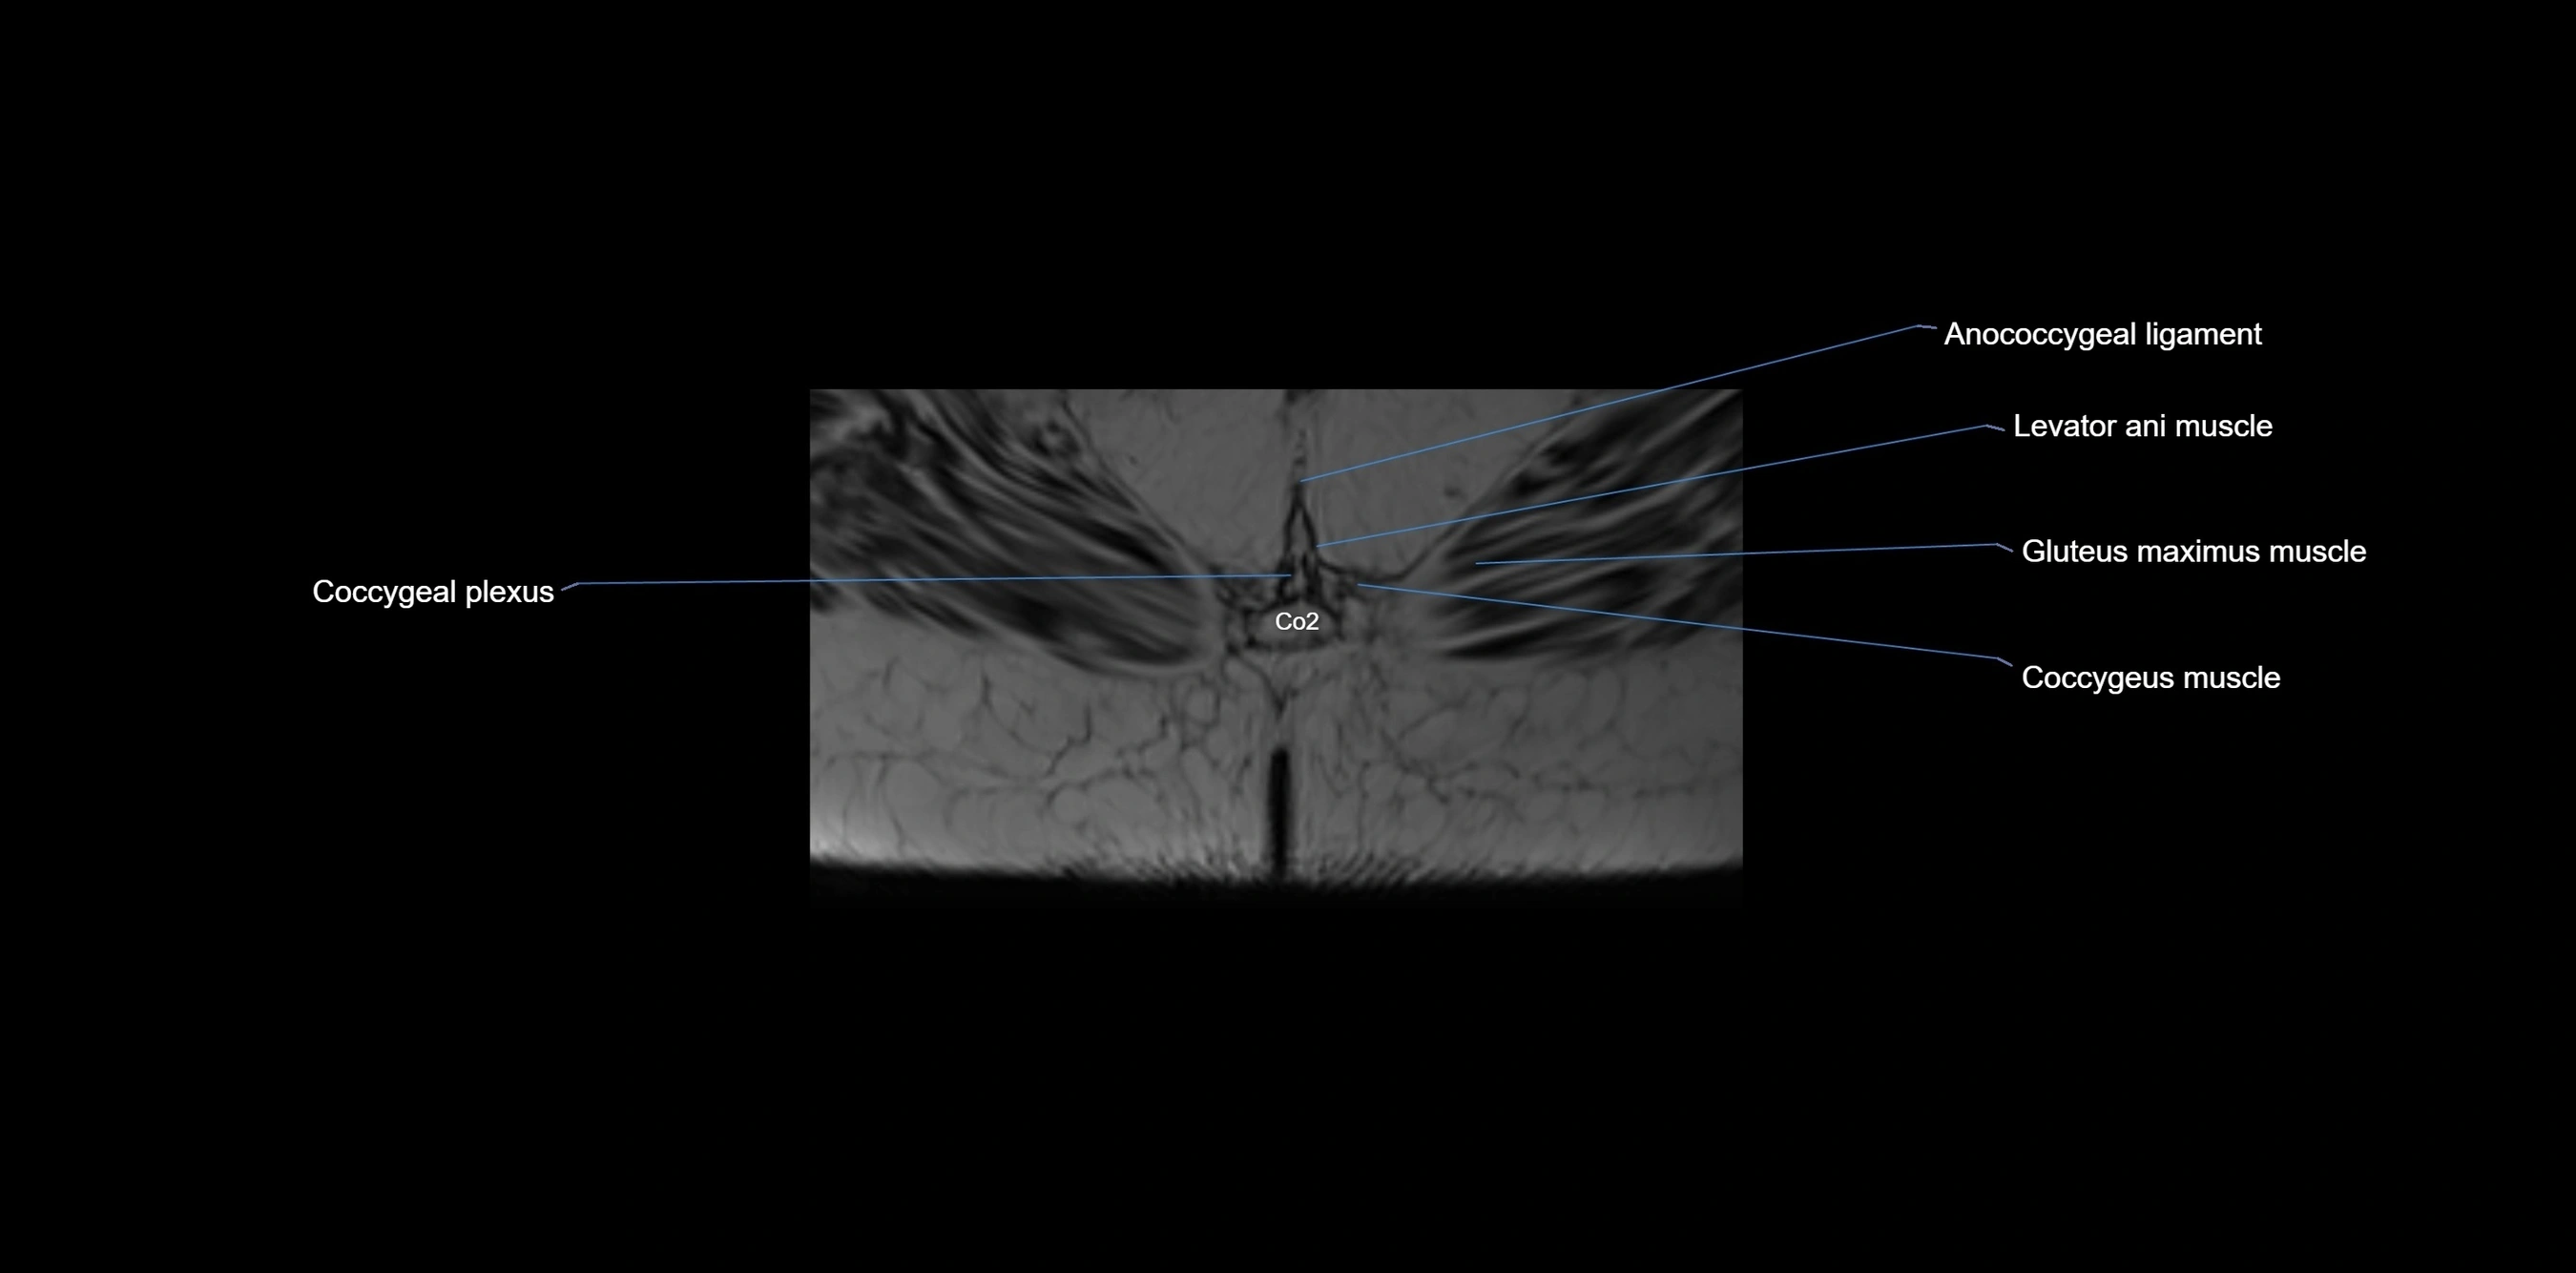

MRI Appearance

T1-weighted images:

• Cortical bone appears very low signal (dark); marrow shows intermediate signal

• Iliac fossa fat is bright against low-signal cortex

T2-weighted images:

• Cortical bone remains dark

• Marrow signal varies depending on fat content; edema or tumor shows hyperintensity

STIR:

• Suppresses fat, making bone marrow edema, fractures, or infiltrative lesions appear bright

• Excellent for trauma, sacroiliitis, and metastatic evaluation

T1 Fat-Saturated (Pre-contrast):

• Marrow: intermediate signal, fat suppressed

• Useful for detecting subtle marrow abnormalities adjacent to iliac cortex

T1 Fat-Saturated Post-Contrast (Gadolinium):

• Enhances vascularized structures, marrow pathology, tumors, and inflammatory changes

• Highlights soft tissue or bone invasion in pelvic neoplasms

MRI Non-Contrast 3D Imaging:

• Provides 3D morphology of iliac wing, crest, and articulations

• Used in preoperative planning for pelvic surgery and trauma reconstruction